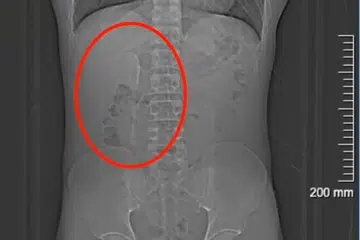

முன்சிறுகுடலில் கரண்டி சிக்கியிருந்தது மருத்துவப் பரிசோதனையில் கண்டுபிடிக்கப்பட்டது.

ஷாங்காய்: குடிபோதையில் காப்பி கலக்கும் கரண்டியைத் தற்செயலாக விழுங்கிய சீன ஆடவர் ஒருவர், ஐந்து